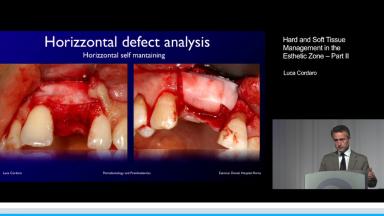

This presentation follows Part I by the same speaker, which focused on timing and soft tissue management for esthetic and posterior areas. Part II focuses on bone augmentation procedures in simultaneous and staged applications for single-tooth cases and partially edentulous patients. This lecture discusses specific indications for different bone augmentation procedures as well as a rationale for selecting a particular technique depending on the clinical situation. The practical approach advocated in this presentation includes both ‘preferred’ and ‘alternative’ treatment approaches.

- recognize indications for bone grafting in relation to implant placement

- describe timing and techniques utilized for bone grafting

- identify degree of complexity and possible complications when performing bone grafts